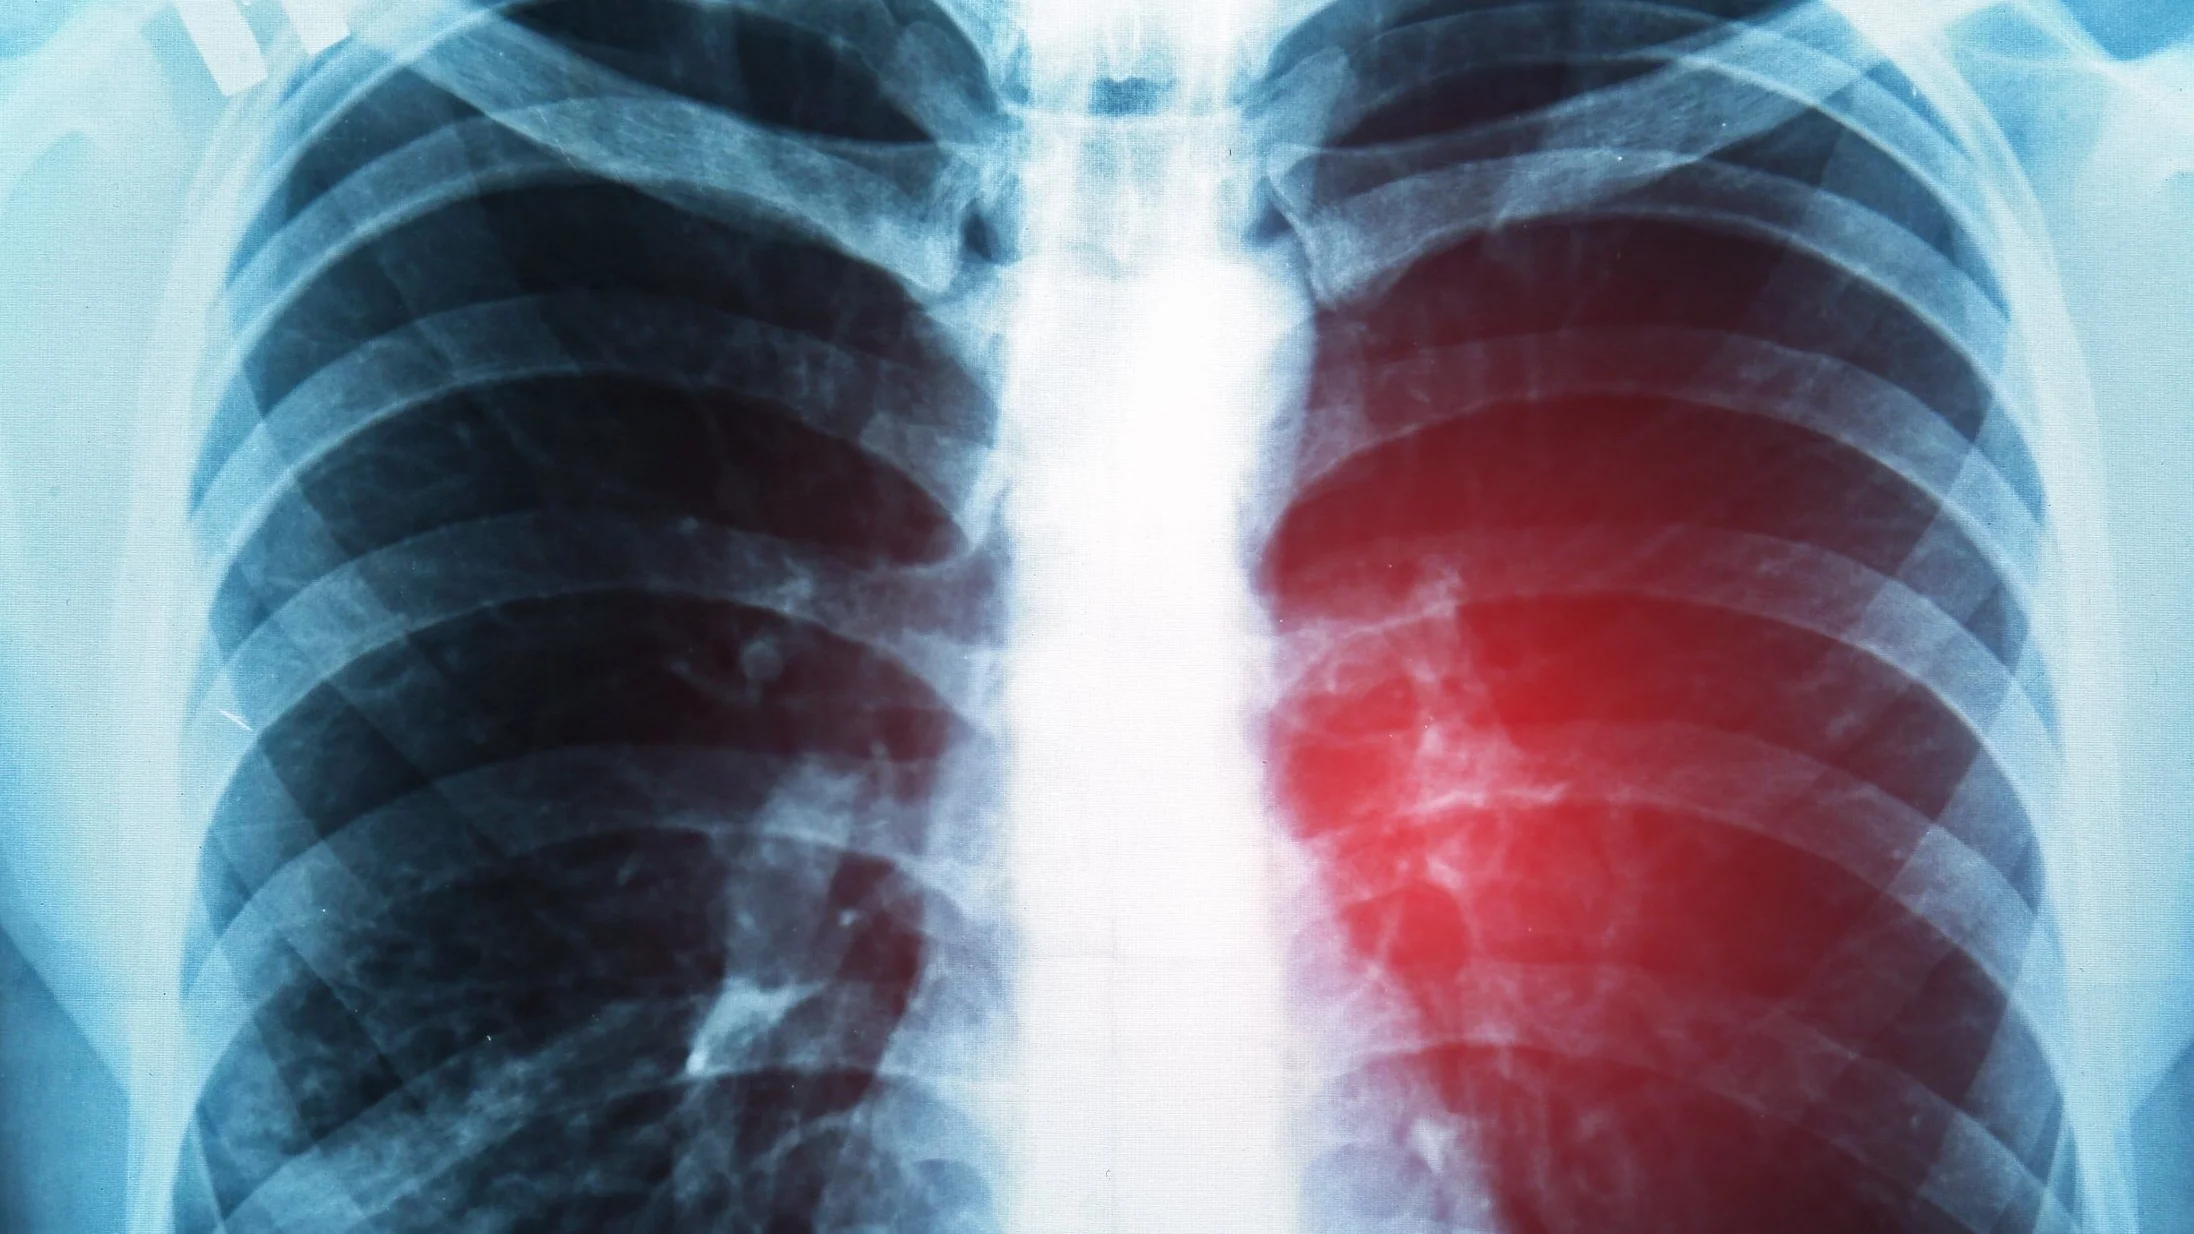

Drobnokomórkowy rak płuca to naj bardziej agresywna postać nowotworu płuc. Jak wygląda jego epidemiologia?

Rak płuca możemy podzielić zasadniczo na dwa typy: niedrobnokomórkowy, który stanowi około 85 proc. przypadków, oraz drobnokomórkowy – ok. 15 proc. W Polsce co roku diagnozuje się blisko 23 tys. nowych przypadków raka płuca, a więc kilka tysięcy dotyczy właśnie postaci drobnokomórkowej. Jest to nowotwór wyjątkowo agresywny, szybko postępujący, który bardzo często rozpoznajemy dopiero w stadium rozsiewu. Typowe są przerzuty do ośrodkowego układu nerwowego, co dodatkowo pogarsza rokowanie.

Rak płuca przez długi czas nie daje objawów.

Tak, bo płuca nie są unerwione – dlatego rak może się rozwijać, nie powodując dolegliwości. Objawy, takie jak duszność, kaszel czy ból, pojawiają się dopiero wtedy, gdy guz jest duży, nacieka ścianę klatki piersiowej albo daje przerzuty do kości lub ośrodkowego układu nerwowego. Zdarza się, że choroba zostaje wykryta przypadkowo – np. podczas badań okresowych. Dlatego tak ważny jest program wczesnego wykrywania raka płuca z wykorzystaniem niskodawkowej tomografii komputerowej (LDCT). Badanie to pozwala wykryć raka na wczesnym etapie, zanim pojawią się objawy. W Polsce program obejmuje osoby powyżej 50. roku życia z wieloletnim nałogiem palenia. Wyniki dużych badań amerykańskich i europejskich potwierdzają, że LDCT zmniejsza śmiertelność z powodu raka płuca o ok. 20 proc.